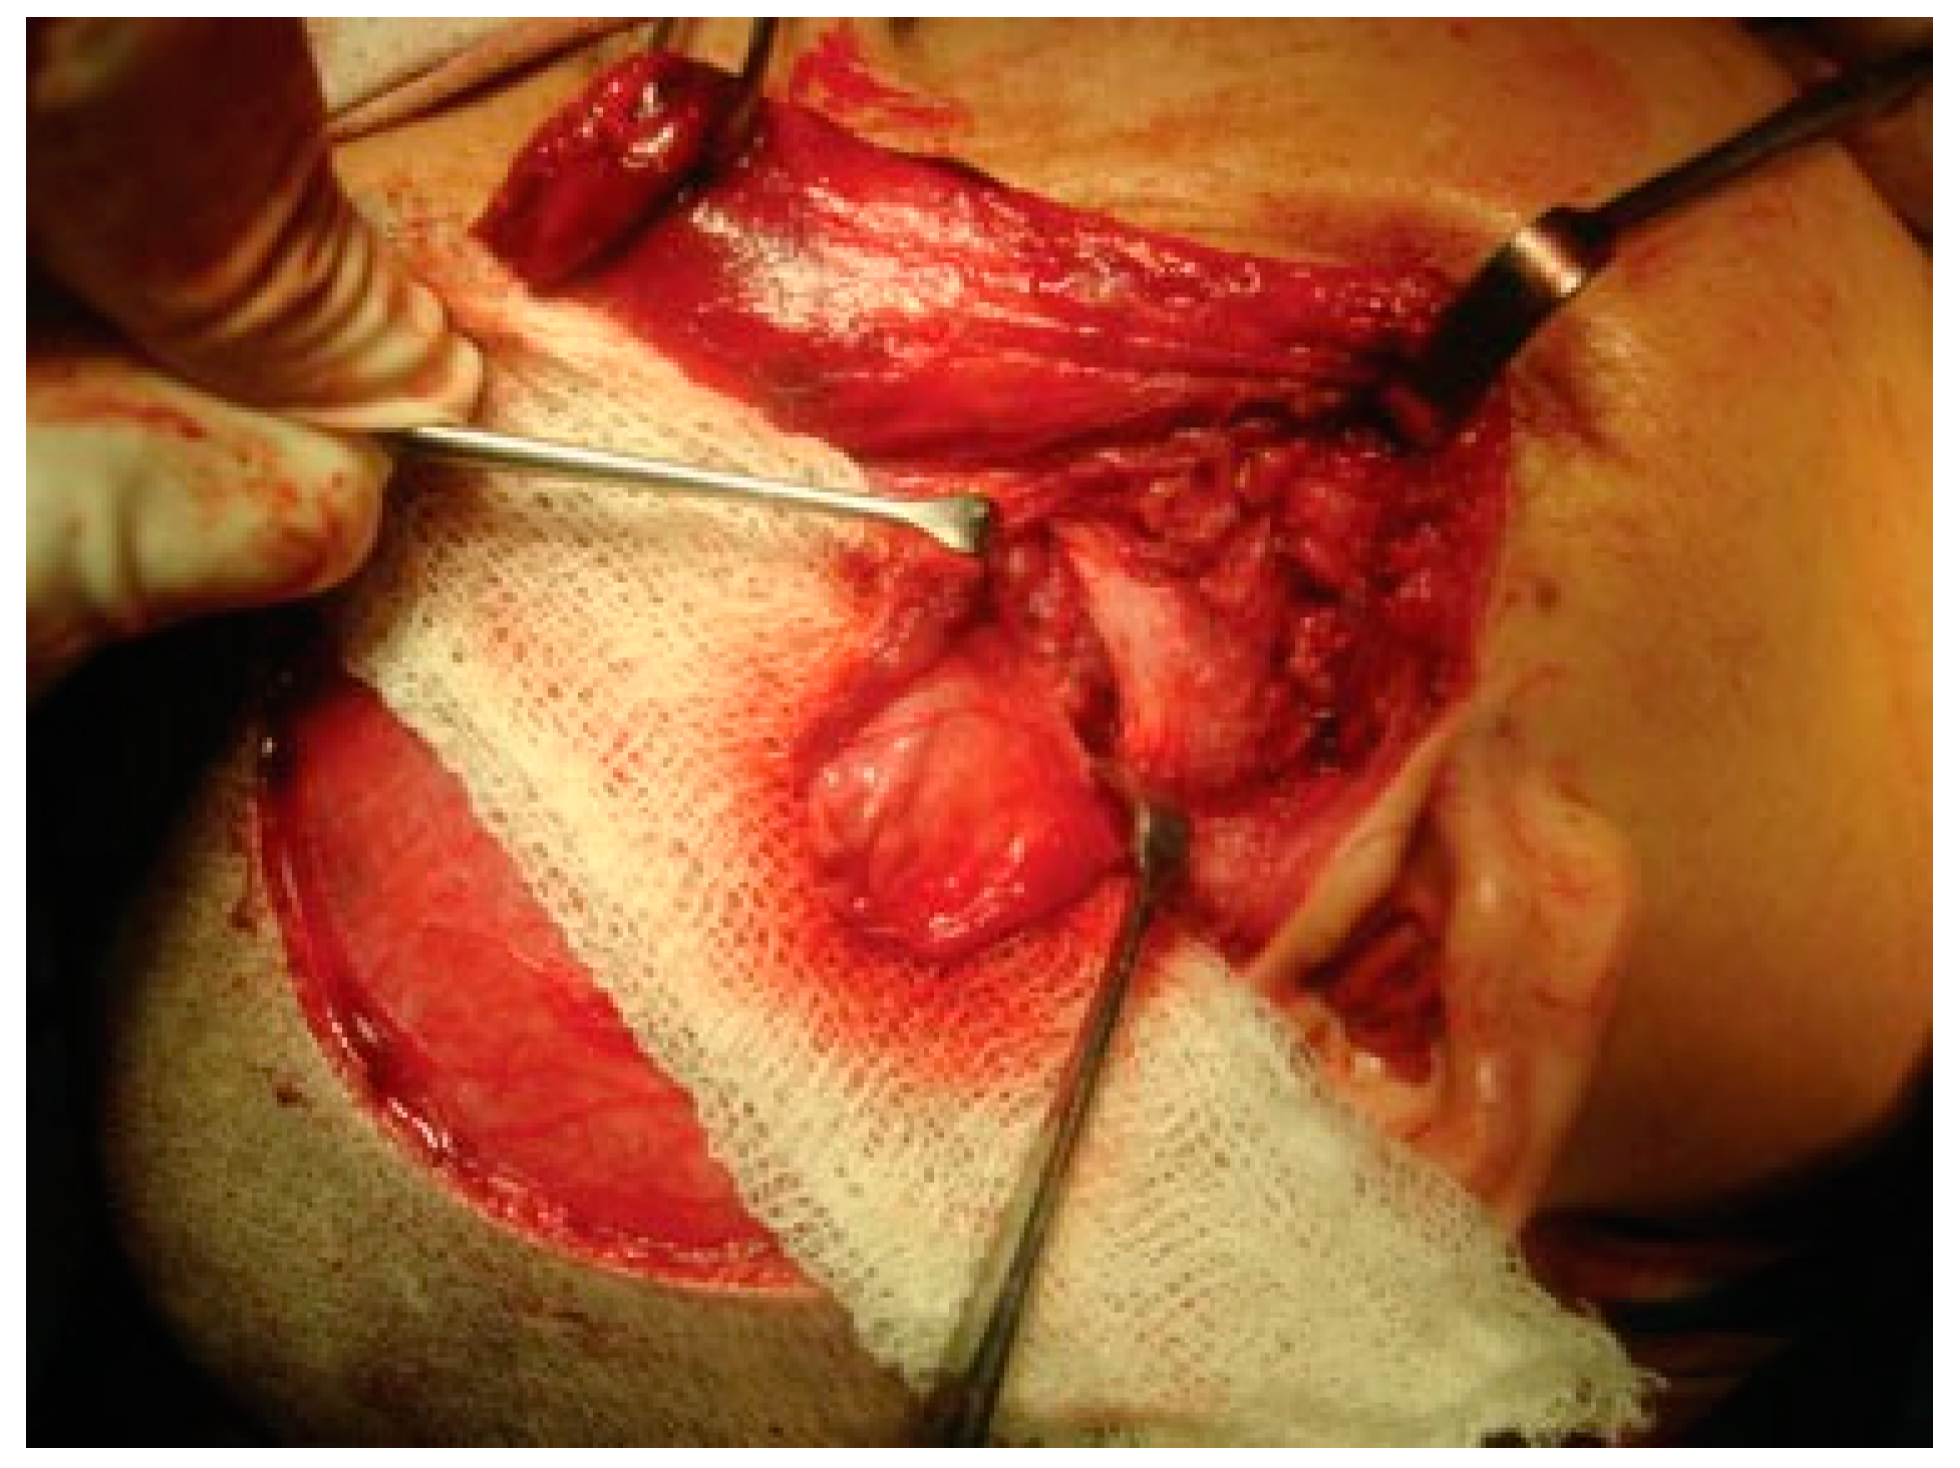

Figure 6. Resected ankylotic chunk with coronoidectomy.

Reconstruction of the TMJ after release of ankylosis assumes paramount importance in terms of restoration of facial form and function. The goals of treatment in all the patients were the release of ankylotic mass, restoration of normal jaw form and function, symmetric growth of the mandible in children, and most importantly the prevention of reankylosis. All interpositional arthroplasties are to some extent the autogenous reconstruction of the morbid ankylotic TMJ after resection of the ankylotic mass. Merriam Webster Dictionary defines reconstruction as the act or process of building something that was damaged or destroyed again. Reconstructive surgery refers to a procedure whose goal is intended to restore form and function in structures deformed or damaged by disease, congenital anomaly, tumor, trauma, or infection (Farlex Partner Medical Dictionary Farlex 2012). The treatment of TMJ ankylosis is individualized based on the severity of ankylosis, age of the patient, and other patient factors. We have outlined our experience following Kaban’s protocol in the management of TMJ ankylosis. It is of paramount importance to obtain passive and maximal mouth opening using this protocol in terms of adequate resection and ipsilateral or contralateral coronoidectomy whenever required followed by aggressive physiotherapy (Figure 5 and Figure 6). Physiotherapy was started on third day postoperatively using Heister mouth gag five times a day during the hospital stay of the patient. This device was purchased by the patient after discharge from the hospital for physiotherapy at home. The MIMO and excursive movements were recorded at various follow-ups for all the patients. No intermaxillary fixation/elastics were applied to any of the patients in the series.